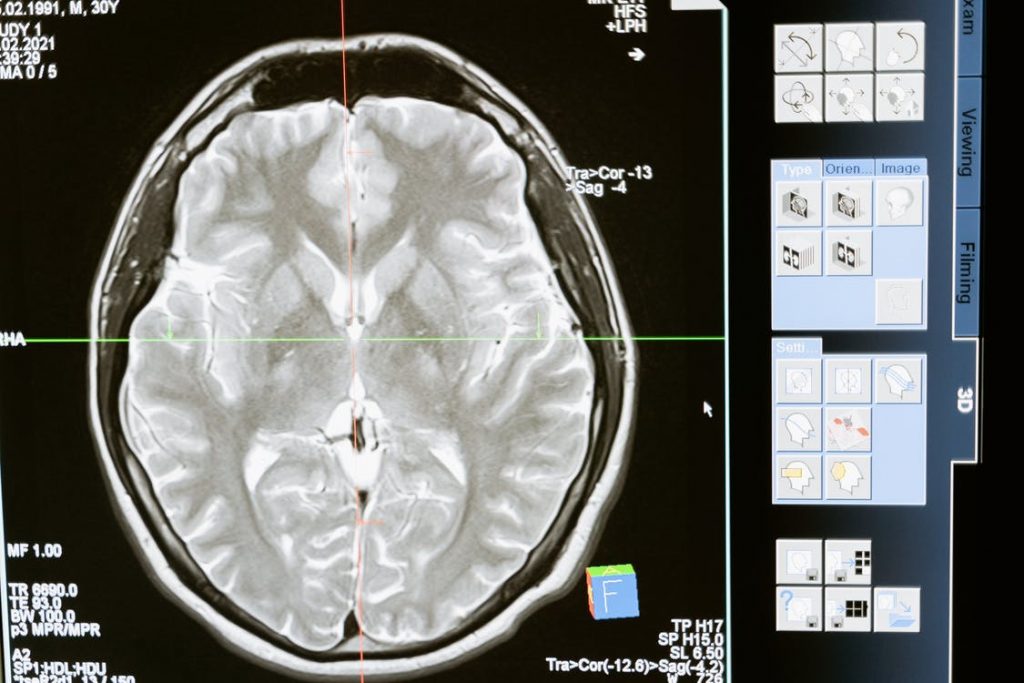

Neurological injuries can have serious long-term negative effects on a person’s health. Classifying head trauma as a neurological injury can mean brain trauma, spinal cord damage, skull fractures, broken bones in the spine, and destruction of the peripheral nerves. There are several ways that a person can suffer a neurological injury such as after a […]